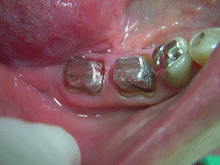

A G C

ガルバノテクニックを用いて作製されるセラミックであり、純金を用いる事によって生体親和性に優れ、歯肉にもやさしく、最適な適合精度と最適なマージン適合性が得られます。